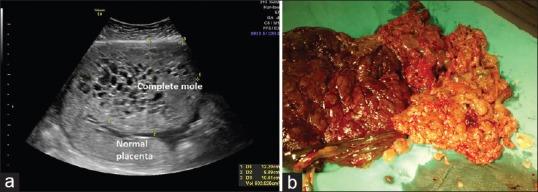

Partial/complete hydatidiform mole with coexisting fetus is a rare condition. Optimal management is a challenge that remains a dilemma since these pregnancies are associated with maternal as well as fetal complications including hemorrhage, preeclampsia, thromboembolic disease, intra uterine demise and increased risk of persistent trophoblastic disease. Here we report 2 cases of partial mole with live fetus after ICSI and a case of complete mole with coexisting fetus after ICSI in a turner mosaic that resulted in a live birth.

部分性/完全性葡萄胎合并存活胎儿是一种罕见情况。最佳管理是一项挑战,仍然是一个两难困境,因为这些妊娠与母体和胎儿并发症相关,包括出血、先兆子痫、血栓栓塞性疾病、宫内死亡以及持续性滋养细胞疾病风险增加。在此,我们报告2例经卵胞浆内单精子注射(ICSI)后部分性葡萄胎合并存活胎儿的病例,以及1例经ICSI后完全性葡萄胎合并存活胎儿的病例,该病例为特纳综合征嵌合体,最终成功分娩。